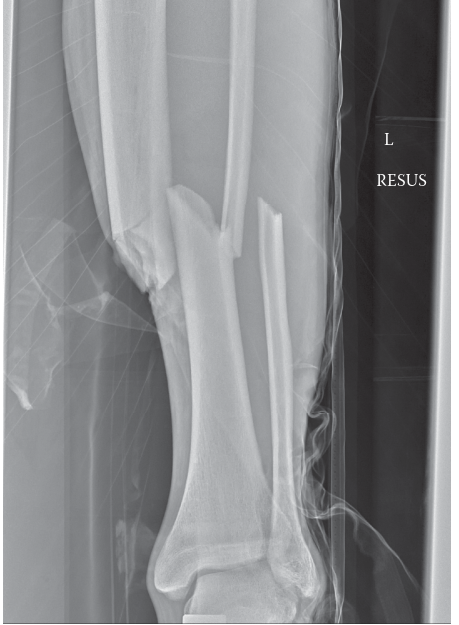

- Image demonstrating fracture reduction or entry point planning: